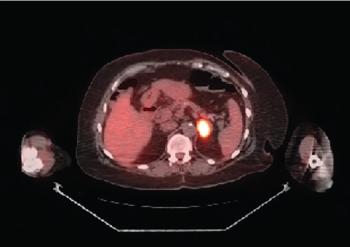

ABSTRACT Gastrointestinal stromal tumors (GISTs) are rare neoplasms of the gastrointestinal tract. They commonly present with nonspecific symptoms and thus are often discovered incidentally. They are best identified by CT scan and most stain positive for CD117 (C-Kit), CD34, and/or DOG-1. Several risk stratification classification systems have been developed based on tumor size, mitotic rate, location, and perforation. Traditional chemotherapy and radiation therapy have been very ineffective, making surgery the mainstay of treatment. The discovery of mutations associated with these tumors has revolutionized the treatment approach. Imatinib mesylate, a selective tyrosine kinase receptor inhibitor, used as adjuvant or neoadjuvant therapy, has greatly improved the morbidity and mortality associated with GISTs. As the survival of patients has increased with the long-term use of targeted therapies, quality-of-life issues now have become much more relevant and have come to the forefront of care. We present a young woman who was successfully treated for GIST but now faces associated long-term adverse effects of imatinib, including the challenge of preserving fertility and the potential for childbearing.